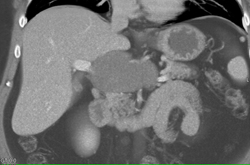

Hepatic Aa Off Single Vessel